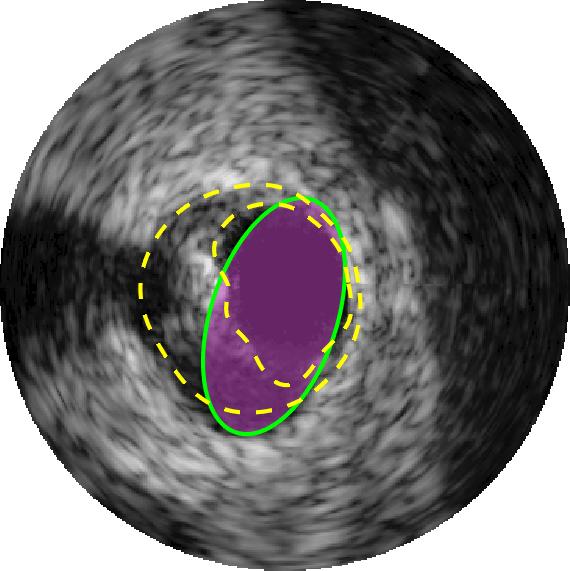

Qualitative evaluations are illustrated in Figure 4 and show the successful segmentation results of the proposed EREL selection strategy for 20 IVUS frames. The lumen areas are highlighted by the magenta colour while the media regions are green. Also, the manually annotated contours for both lumen and media are drawn as yellow dashed lines. As we can see, the chosen frames contain a variety of lumen and media morphologies.